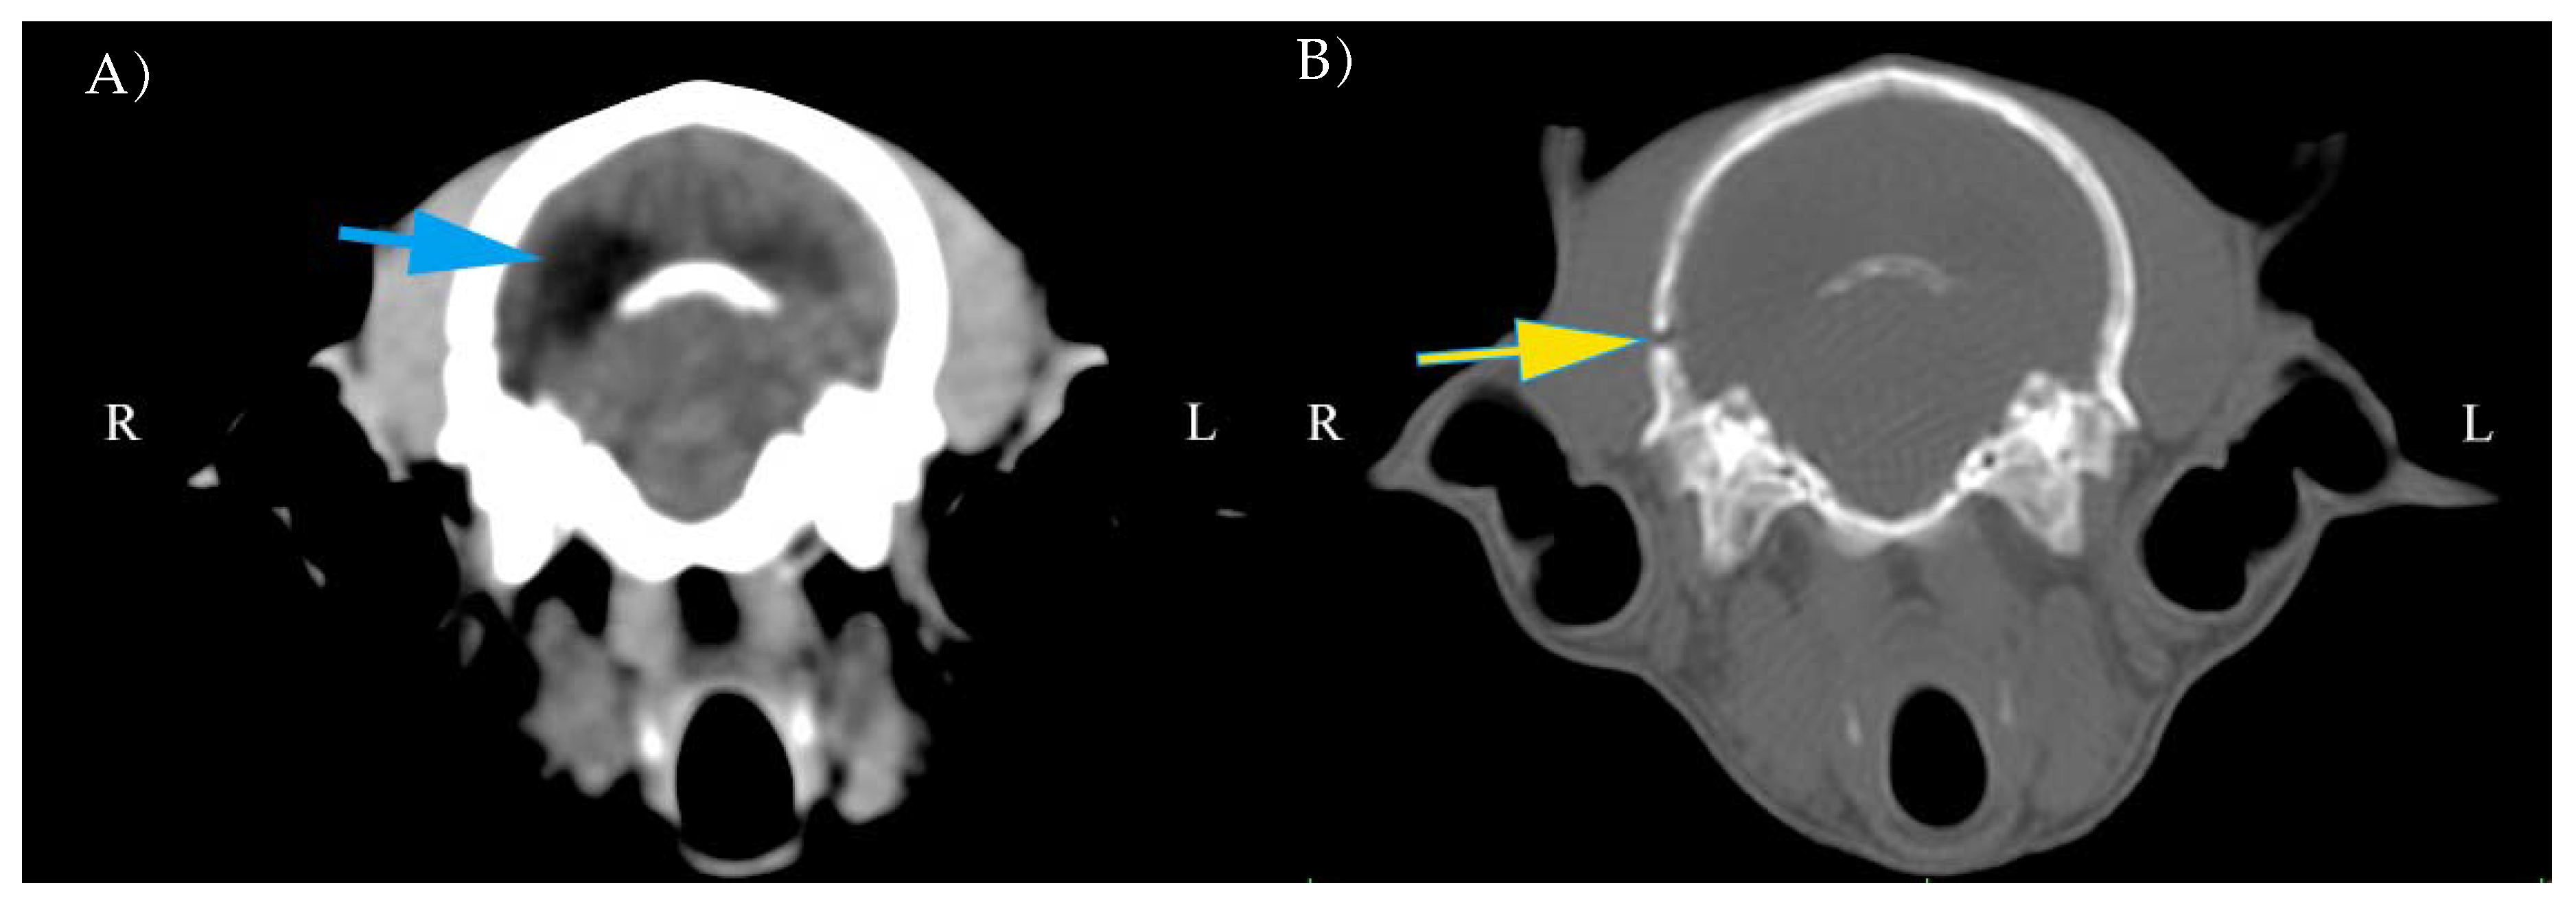

3.3. CT Findings

| Intracranial hemorrhage | |||

| Mild | Moderate | Severe | |

| Intra-axial | 3 (50%) | 3 (50%) | 0 |

| Extra-axial | 2 (33%) | 1 (17%) | 1 (17%) |

| Other findings | |||

| Midline shift | 2 (33%) | 1 (17%) | 0 |

| Lateral ventricle asymmetry | 2 (33%) | 1 (17%) | 2 (33%) |

| Hydrocephalus | 1 (33%) | 1 (17%) | 2 (33%) |